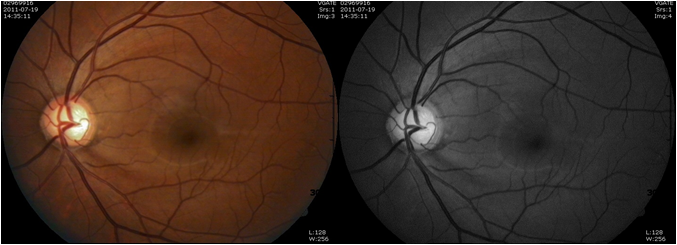

녹내장은 진행될수록 시신경유두가 녹내장성 손상을 보이기 때문에 시신경유두검사가 필요하며, 녹내장이 진행하면서 망막신경섬유층의 두께가 얇아지는 현상을 측정하기 위한 망막신경섬유층 검사가 진단에 유용한 검사다. 이와 함께 녹내장에 있어 가장 중요한 위험요소는 안압이다. 정상안압 녹내장 환자는 안압이 정상 범위라고 해도 환자의 안압이 병의 진행에 있어 가장 큰 위험인자이기 때문에 안압 측정이 매우 중요하다. 위와 같은 여러 안과 검사 결과를 토대로 안과 전문의가 종합적으로 판단하여 정상안압녹내장을 진단하게 된다.